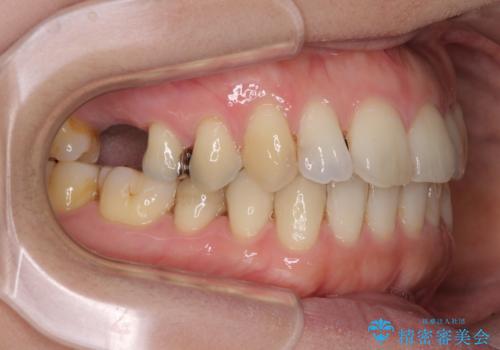

- 上下奥歯の欠損を気にして来院された患者様です。

以前矯正した後戻りにより前歯に叢生が認められたため、矯正治療の提案をしたところ、補綴治療と合わせて矯正治療を行うこととしました。

下顎欠損部はインプラントにて、上顎中間欠損部はブリッジによる補綴治療を行い、他にも気になっている銀歯をセラミックインレーやゴールドインレーにて修復治療を行うこととしました。

後戻りの程度は軽度であったため、インビザライン・ライトを用いて歯列を整えました。

再度後戻りするリスクを最小限に食い止めるため、下顎前歯の舌側を細いワイヤーで固定しました。